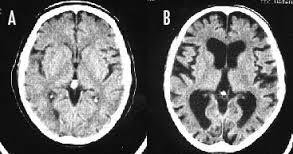

>>4330 大脳皮質が薄くなり認知機能が落ちる 『たばこ脳』 ※写真は左Aが正常の脳、右Bが喫煙者の脳です。 左の脳と比べて右の脳は隙間だらけになってしまっています。

--- 「喫煙者の脳」やはり異変が起きていた(石田雅彦) - Yahoo!ニュース ---

タバコを吸うと脳がすっきりするのは真っ赤な嘘だ。研究によれば喫煙者の脳では明らかに異常が起きている。認知機能も低下し、大脳皮質が元に戻るのには25年もかかる。一刻も早くタバコなど止めたほうがいい。